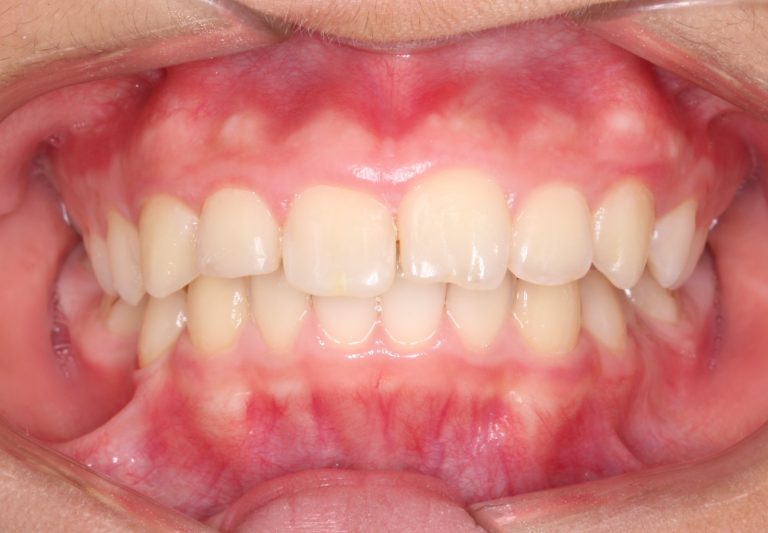

Classe II div 1, articulé croisé postérieur, surplomb accru, déviation de la ligne médiane maxillaire, rotations d'encombrement

Résultats obtenus

- Relation de classe I obtenue

- Guidage fonctionnel des canines des deux côtés

- Articulé postérieur corrigé

- Surplomb et recouvrement normaux obtenus

- Surplomb amélioré

- Lignes médianes coïncidentes

- Bonne inclinaison axiale des incisives

- Courbe de Spee nivelée

- Forme de l'arcade améliorée

- Cas où tous les objectifs du traitement ont été atteints

- Des arcades harmoniques ont été obtenues

État final